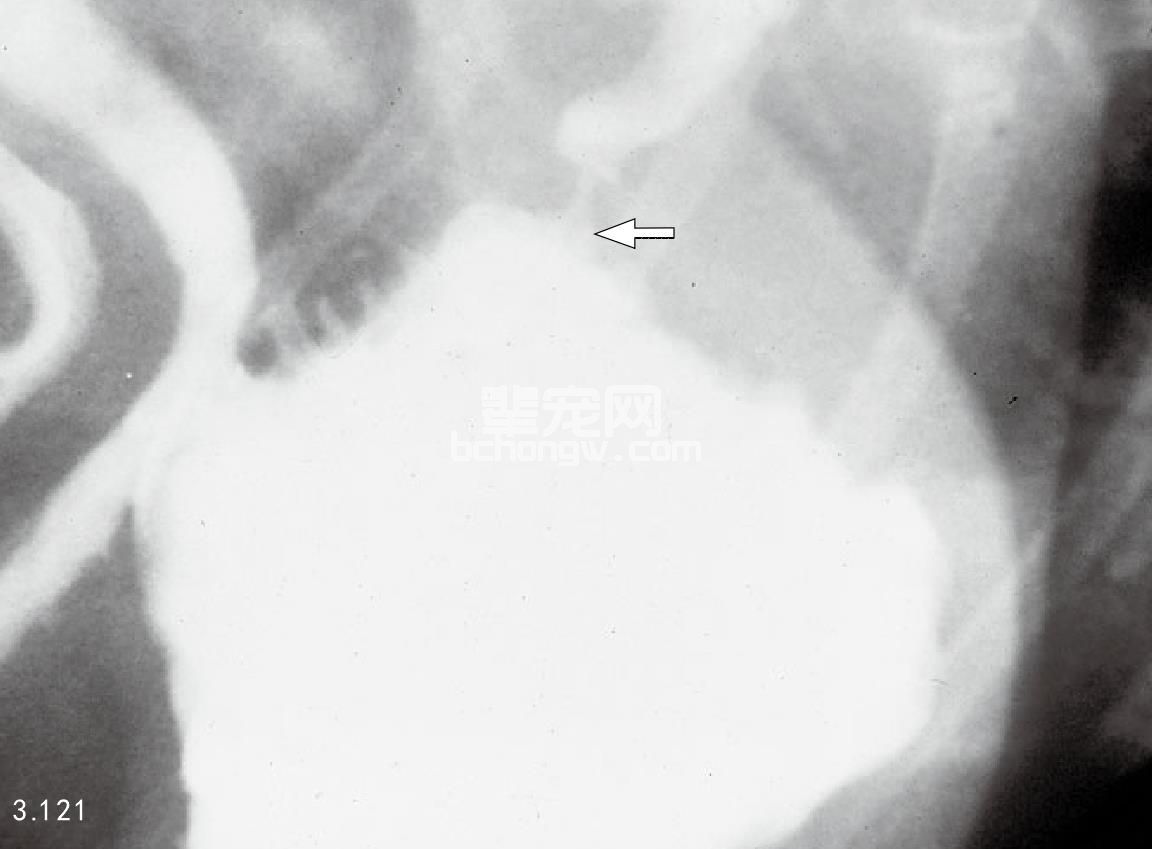

图3.121 图3.119中提到的犬造影X线片:幽门窦膨胀、幽门道狭窄,形成了典型的喙状突或乳头状影像(箭头所指)。